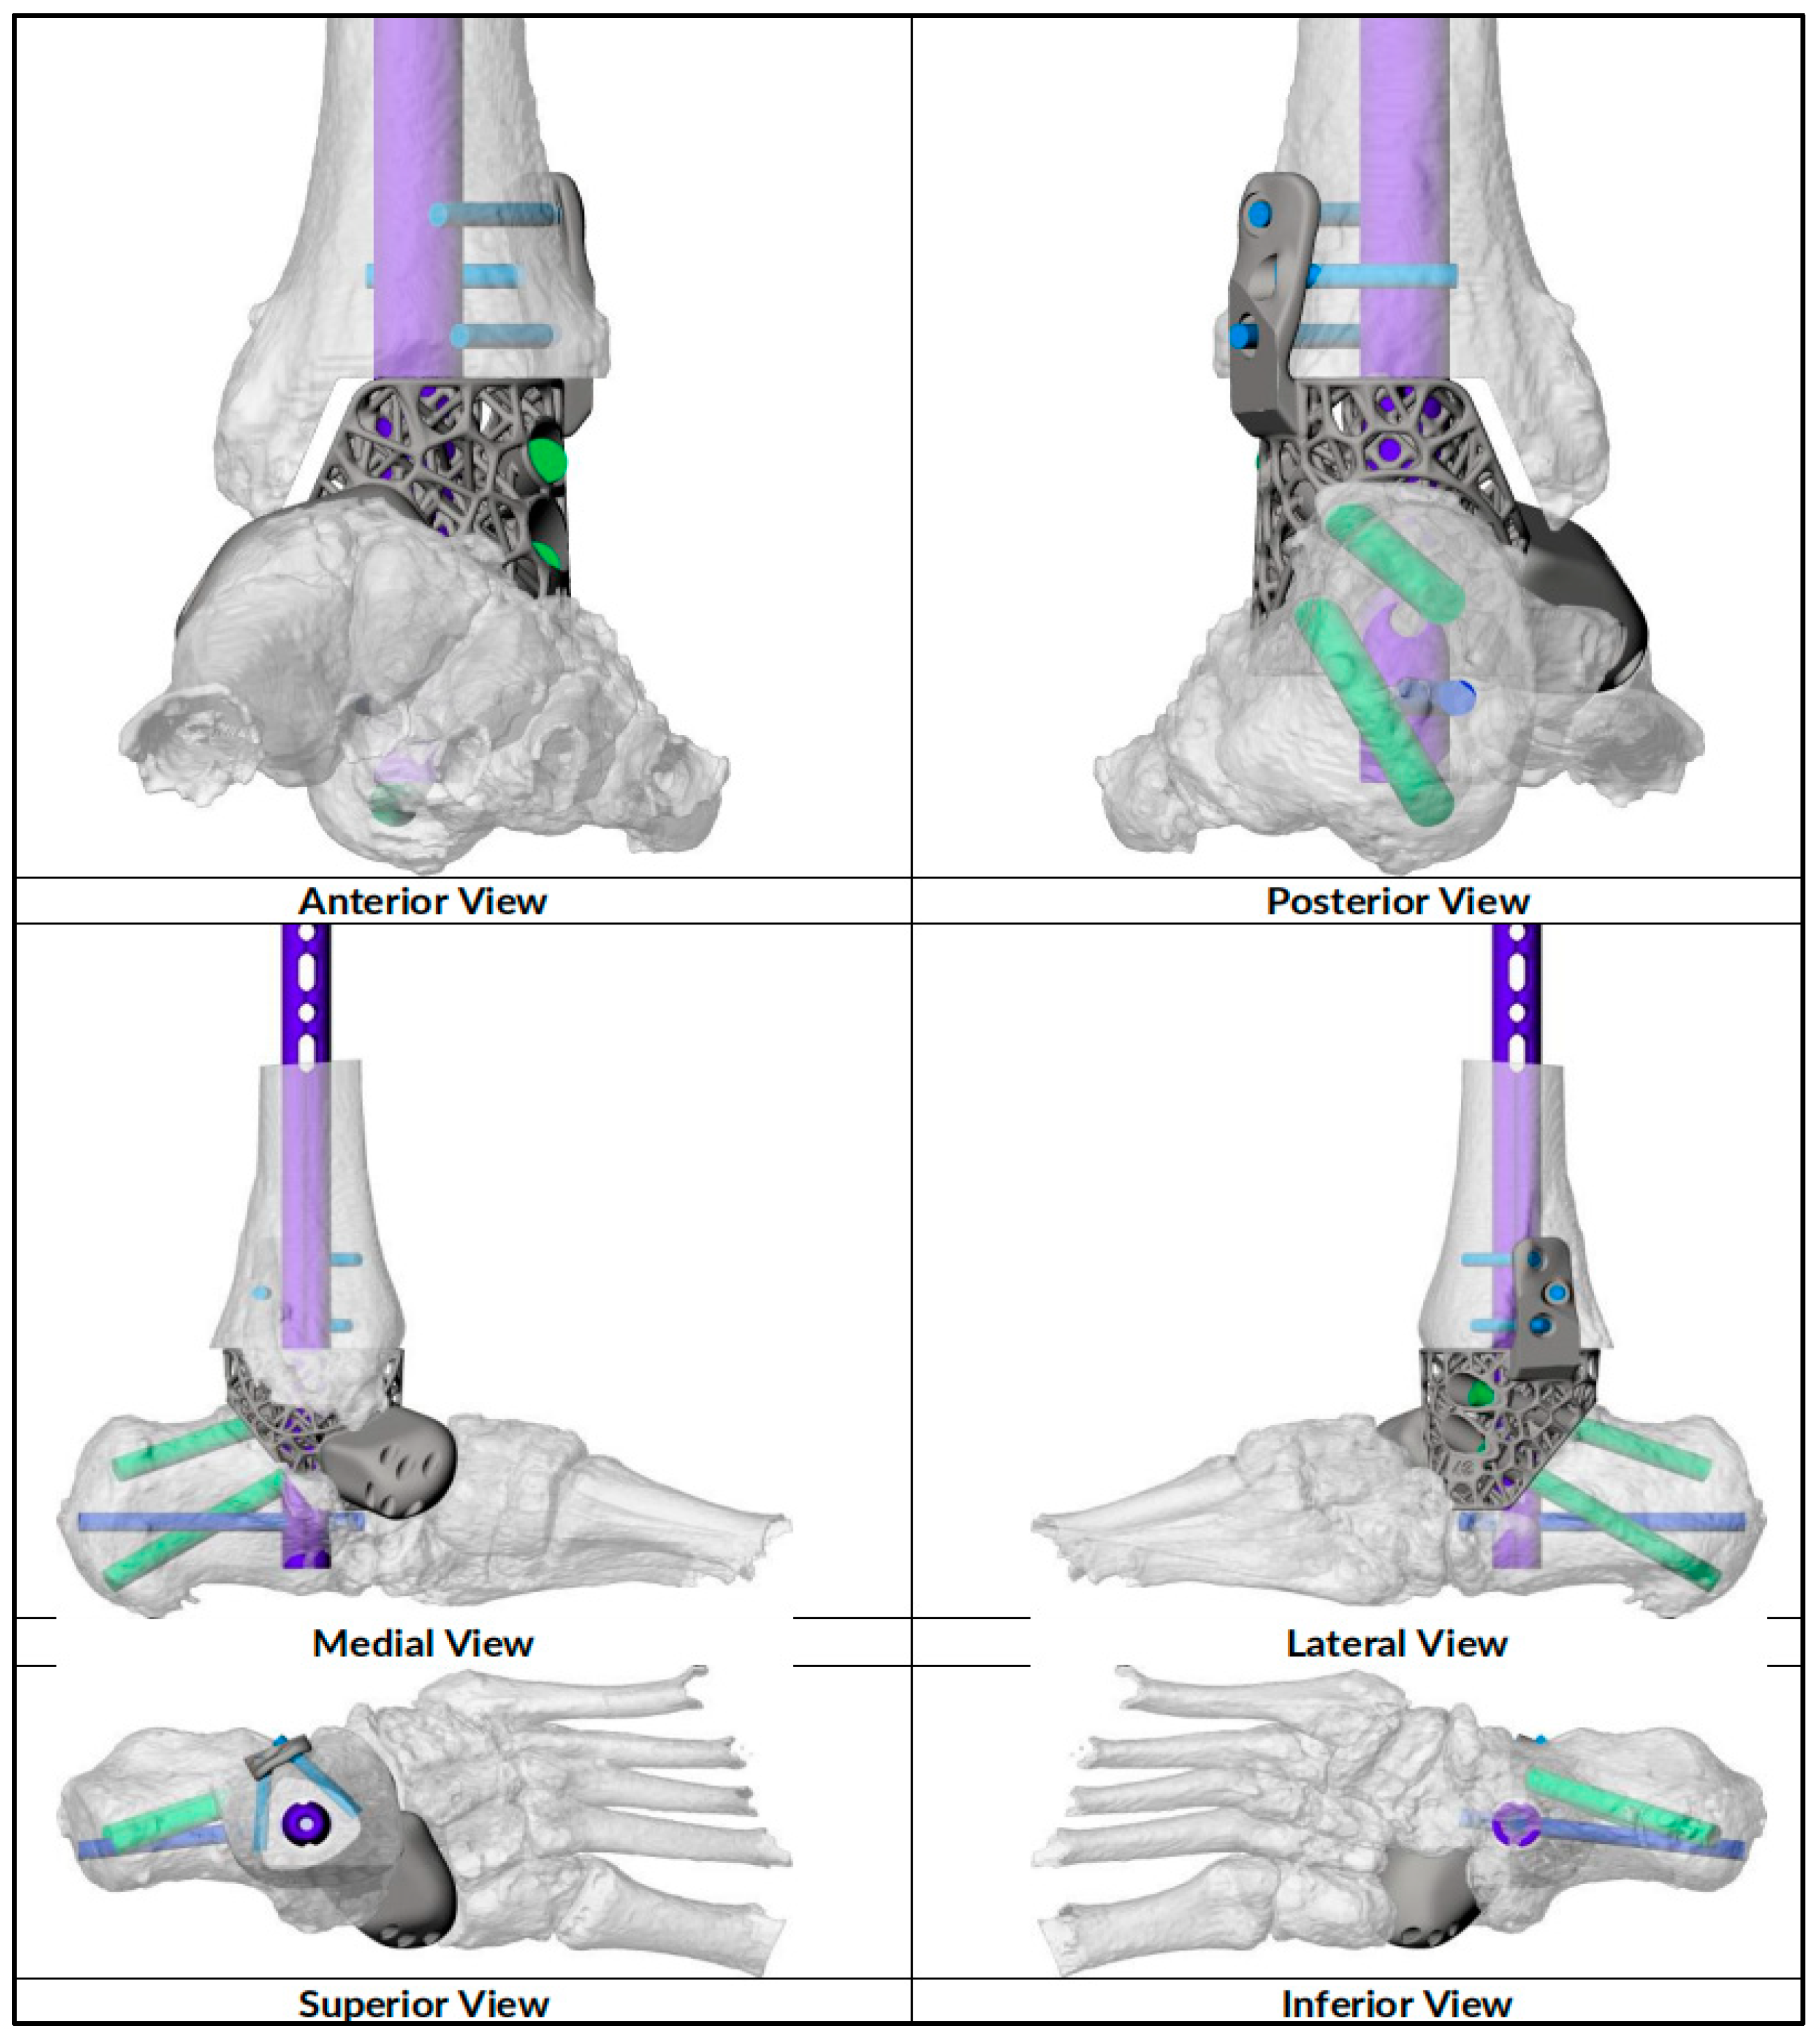

2.1. Preoperative Planning

2.2. Surgical Technique